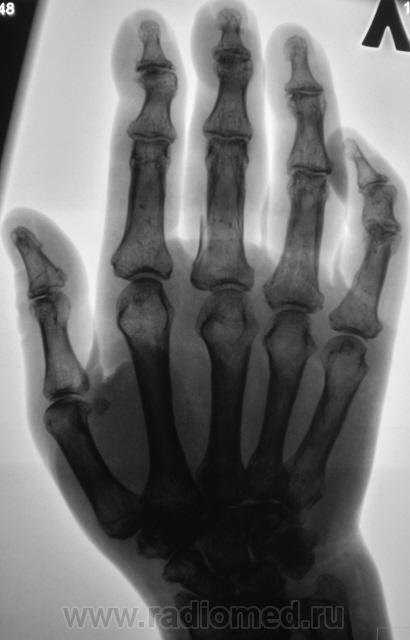

Травма. пациентка направлена на рентгенографию кисти.

здесь очень сложно представить механизм травмы для данного перелома "недолом" какой то, может нужно подумать о патологическом процессе?

А сколько переломов по числу, и что поломано....

Переломов три - о/ф 3, 4, 5 пальцев